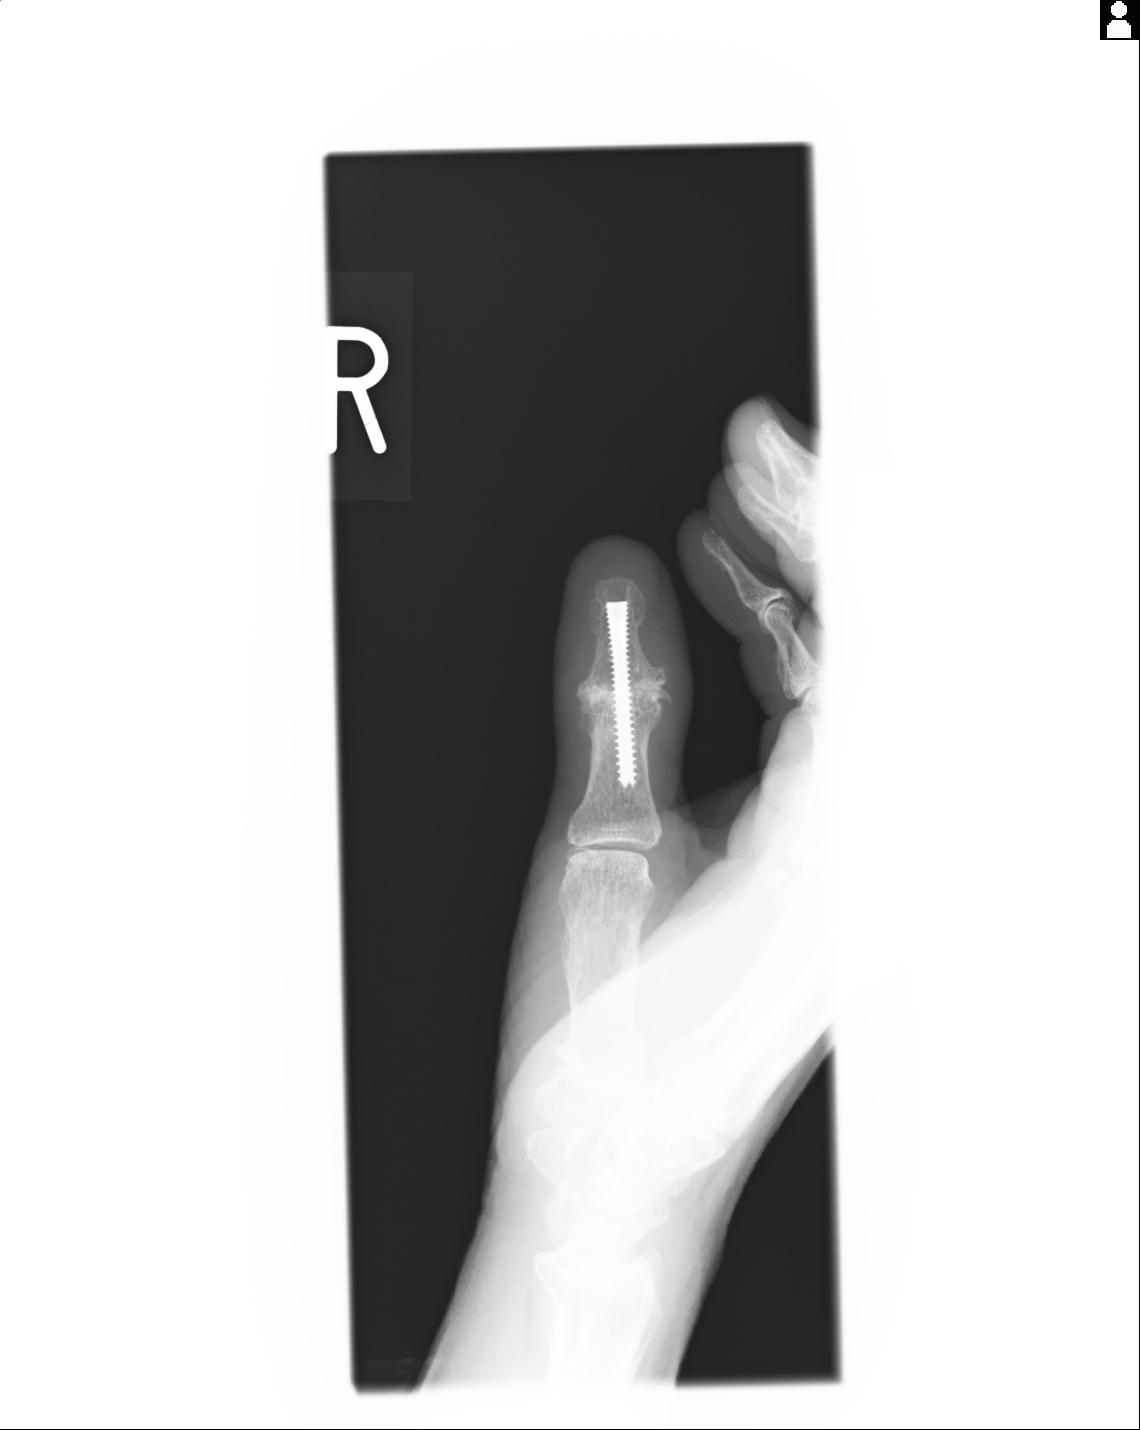

20857 1/11 左手 3R 1/19 4R 55歳男性 小指中節骨骨折